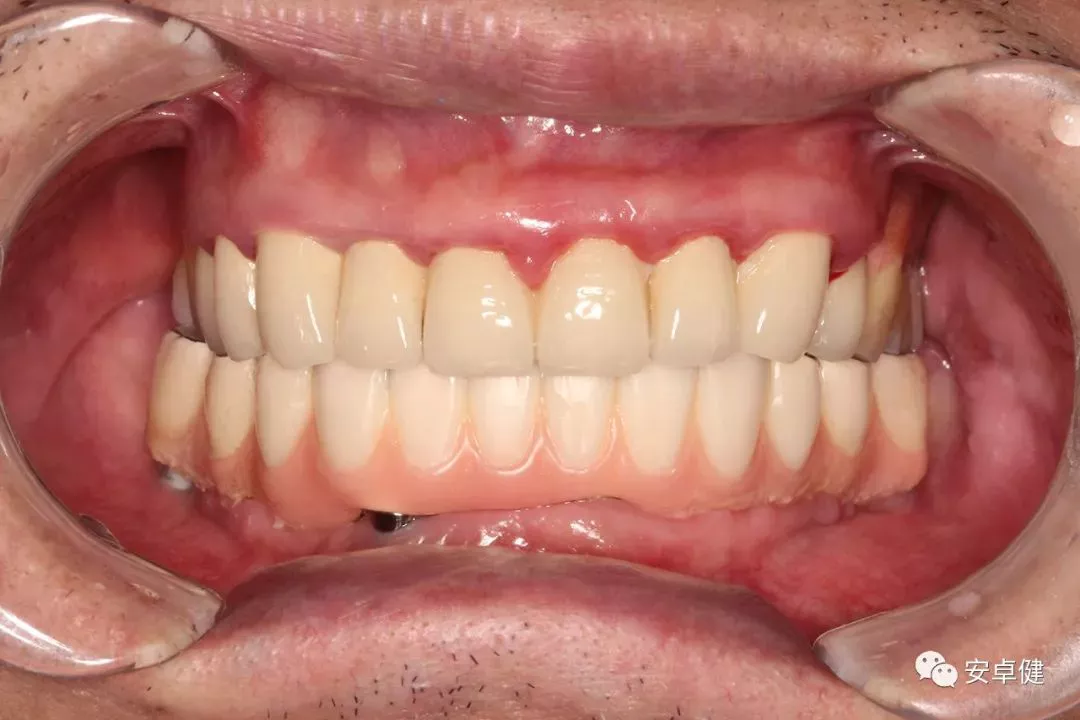

▷ 永久修复

患者术后16个月:

• 于口内试戴原厂纯钛切削一体式桥架,并检查前牙排蜡外形及后牙咬合关系;

• 聚合瓷烤塑制作最终修复体;

• 为减少牙面磨耗,于后牙区制作360度防裂纯钛金属带;

• 试戴满意后,二级螺丝加力至15N;

• 特氟龙封闭螺丝孔,光固化复合树脂封闭上方螺丝通道,完成最终固定式种植义齿修复;

• 修复体外形能够正确恢复面下1/3高度及侧貌;

• 患者可获得较为稳定的咬合关系,并满足其咀嚼功能的需求;

• 患者42、46部位牙龈退缩,缺乏足够的角化龈,为方便后期清洁维护,选择穿龈较高的龈上肩台;

• 口内观察,修复体边缘金属基台颜色暴露,但由于其处于下颌后牙非微笑暴露区,故对临床整体美观效果的影响在患者可接受范围内。